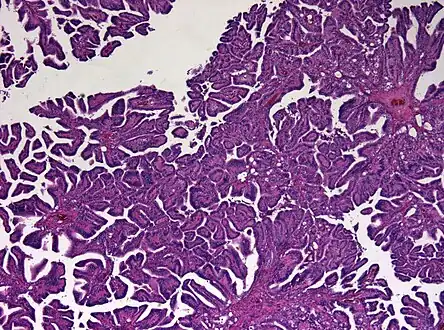

The tumor is neuroectodermal in origin and similar in structure to a normal choroid plexus. They may be created by epithelial cells of the choroid plexus.

Micrograph of a choroid plexus papilloma. H&E stain. -

Plexuspapillom Detail -

Plexuspapillom Overview